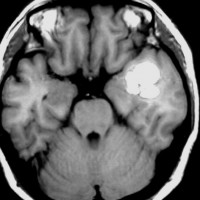

海綿状血管腫はMRIの撮影条件によっていろいろな見え方をします

腫瘍から少し出血したために,患者さんはけいれん(てんかん発作)を起こしました。左のT1強調画像では出血を疑います。中央のT2強調画像では海綿状血管腫の周りに脳浮腫があるために白くぼやけた部分があります。右の造影剤を使ったMRIでは造影剤が入るところがほどんど無いことがわかります。側頭葉の海綿状血管腫は側頭葉てんかんという症状で発症することが多いです。